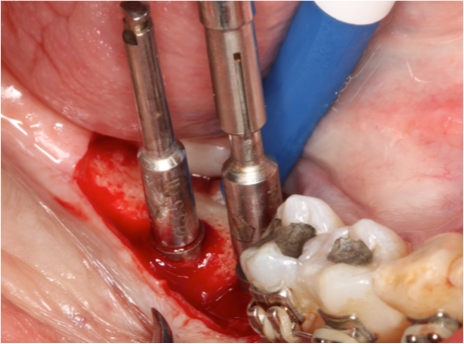

Fig 3, 4 e 5 Observar o posicionamento da broca e o posicionamento do implante com a parte cervical voltada para a lingual e o ápice para vestibular, passando do lado do nervo alveolar.